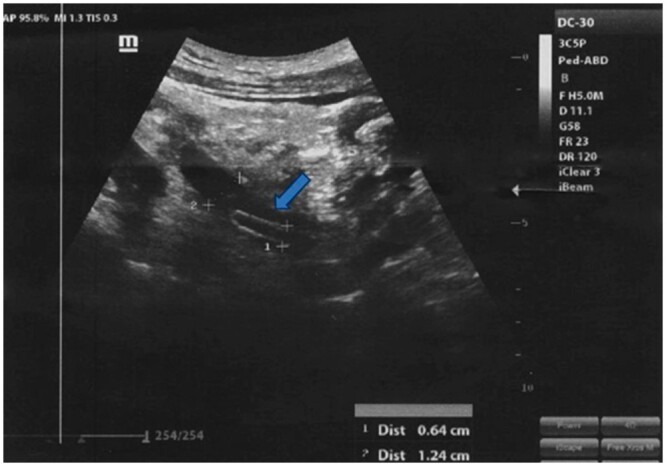

类蚓蛔虫是影响人类的最著名的寄生虫之一。蛔虫病在水、环境卫生和个人卫生不足的发展中国家流行,这些国家便于人与人之间的传播。在此报告中,我们报告了一个20岁男性的病例,他因严重的右侧疼痛,高烧和反复呕吐而到达急诊室。进行诊断评估,包括全血细胞计数测试、尿液分析、粪便分析、腹部超声和CT扫描。最终诊断为输尿管远端发现类蚓状瘤。输尿管镜检查证实了诊断并取出了蠕虫,该蠕虫长6厘米,呈棕色,并表现出紧密的弹性一致性。蛔虫通常在胃肠道中发现,但在尿道中出现是一种极其罕见的现象。在我们的病例中,最可能的解释是蛔虫通过逆行迁移进入输尿管远端,其中蛔虫从膀胱进入输尿管。

Ascaris lumbricoides is one of the most well-known helminthic parasites affecting humans. Ascariasis is prevalent in developing countries where inadequate water, sanitation, and hygiene facilitate human-to-human transmission. In this report, we present a case of a 20-year-old male who arrived at the emergency room with severe right flank pain, high-grade fever, and recurrent vomiting. Diagnostic evaluations were conducted, including a complete blood count test, urinalysis, stool analysis, abdominal ultrasound, and CT scan. The final diagnosis was A lumbricoides found in the distal part of the ureter. A ureteroscopy procedure confirmed the diagnosis and extracted the worm, which measured 6 cm in length, had a brown colour, and exhibited a tight elastic consistency. While Ascaris is commonly found in the gastrointestinal tract, its occurrence in the urinary tract is an extremely rare phenomenon. In our case, the most likely explanation is that the Ascaris accessed the distal ureter through retrograde migration, wherein the worm traverses from the bladder into the ureter.